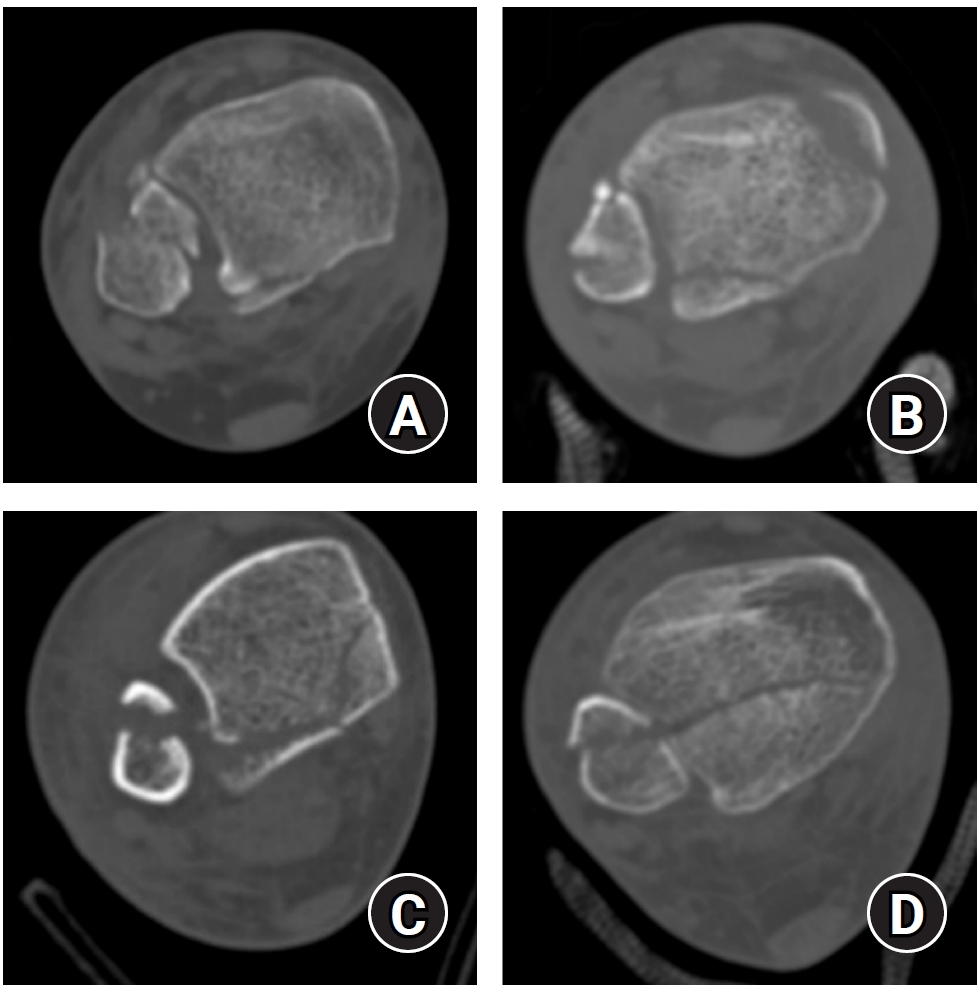

Posterior malleolar fracture morphology was classified according to the Haraguchi and Bartonicek systems (Figs. 2, 3) [19,20]. The peak height of the posterior malleolar fracture was measured as the vertical distance from the highest point of the distal tibial articular surface to the fracture apex in the sagittal plane (Fig. 4A). The articular surface area of the posterior malleolar fragment was calculated using the region of interest tool in a picture archiving and communication system (Maroview 5.4; INFINITT Healthcare) (Fig. 4B). All quantitative radiographic measurements were performed by two orthopedic surgeons; mean values were used. For categorical variables, disagreements were resolved by consensus.

Fig. 2.

Haraguchi classification of posterior malleolar fractures. (A) Type I: posterolateral-oblique type. (B) Type II: medial-extension type. (C) Type III: small-shell type.

Fig. 2. Haraguchi classification of posterior malleolar fractures. (A) Type I: posterolateral-oblique type. (B) Type II: medial-extension type. (C) Type III: small-shell type.